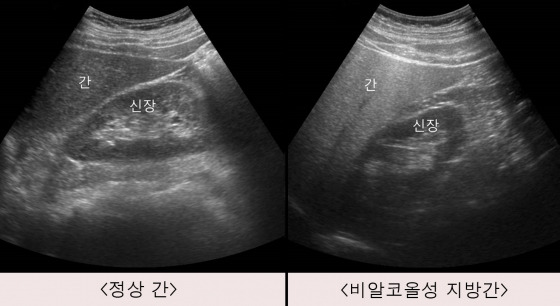

지방간은 간세포에 지방이 과도하게 축적된 상태를 말합니다.

일반적으로 간 지방 비율이 5% 이상이면 지방간으로 진단됩니다.

지방간은 크게 두 가지로 나뉩니다.

- 알코올성 지방간 : 음주가 주된 원인

- 비알코올성 지방간 : 비만, 당뇨, 고지혈증, 인슐린 저항성

최근에는 술을 거의 마시지 않아도 생기는

비알코올성 지방간이 훨씬 더 많습니다.